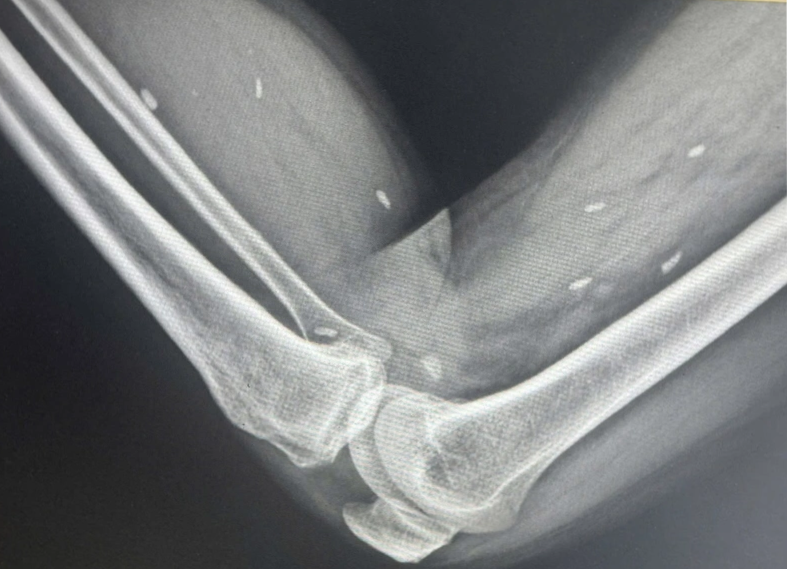

Trước đó, ông T.T.H đến Trung tâm Y tế khu vực Thạch Hãn thăm khám trong tình trạng mệt mỏi kéo dài, đau nhức nhiều ở vùng chân và lưng, vận động khó khăn. Qua thăm khám lâm sàng, các bác sĩ đã chỉ định chụp X-quang cho ông H. để tìm nguyên nhân.

Kết quả cho thấy nhiều kén sán có kích thước tương đương hạt gạo, nằm rải rác trong các mô mềm vùng xương đùi và cẳng chân. Bác sĩ nhận định đây là hình ảnh điển hình của tình trạng nhiễm kén sán.